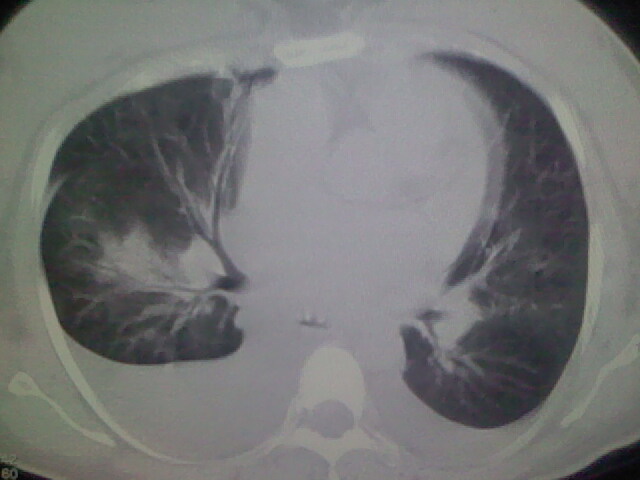

女,24,剖腹产后,突觉胸痛,干咳,不能平卧

临床资料及影象表现支持围产期扩张型心肌病改变,心衰。

考虑产后心肌病,心功能不全,肺水肿,双侧胸腔积液。

考虑产后心肌病,心功能不全,肺水肿,双侧胸腔积液。不排除羊水栓塞可能。